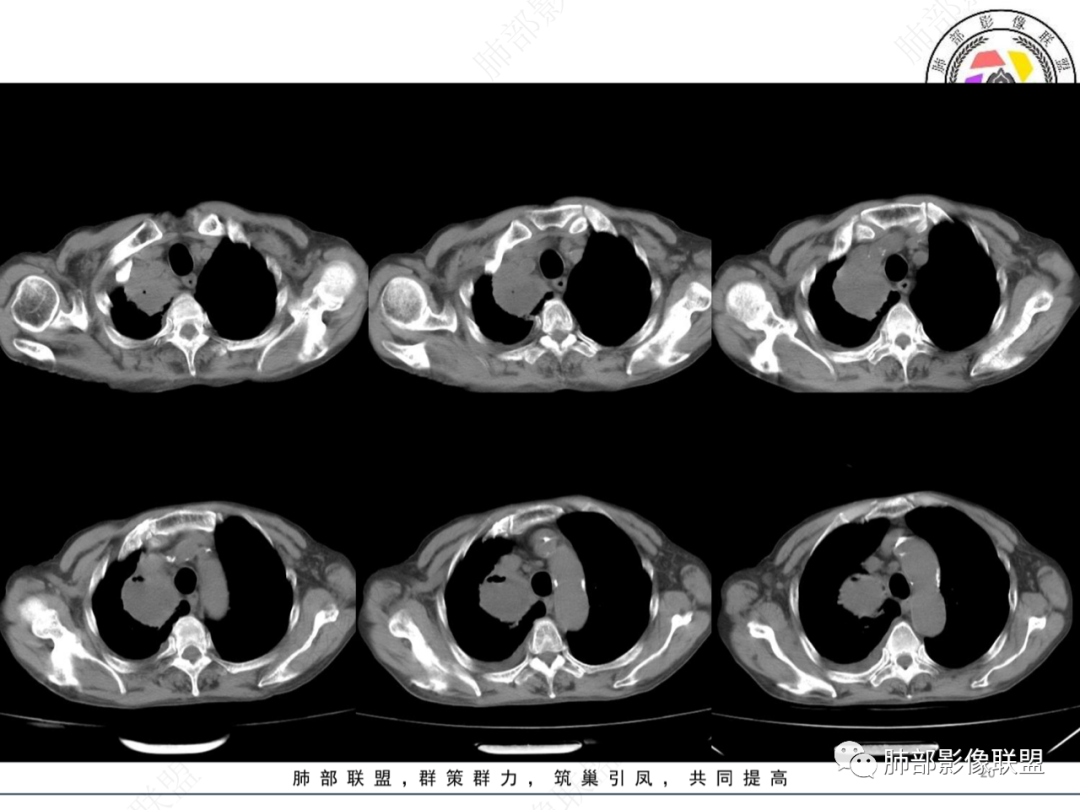

主病灶在右上叶尖段、前段纵隔旁,紧贴胸膜

楔形、边缘膨隆,附近见斑片状、网格状高密度影

支气管近端堵塞,可惜显示的不一定全面

支气管壁还是弥漫增厚

中央坏死明确

如果更薄层一些就好

整体内壁偏清楚,似乎有些地方欠清,不知道是否厚层所致

整体而言:远侧、内侧壁厚

坏死明显,这类膨隆就不支持生长速度不一致所致,而支持坏死朝周围的压力导致边缘的膨隆

这里倒是符合血管的压迫

与胸膜的关系?分界还算清楚

符合炎性的地方:整体形态,可惜重建的图太少

坏死内壁光滑、周围炎性改变